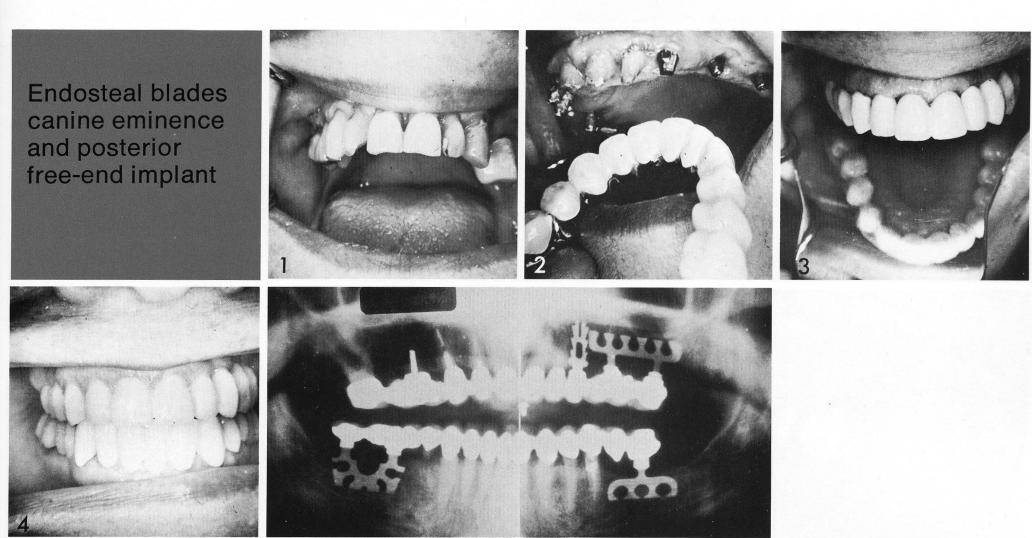

Endosteal blades canine eminence

and posterior free-end impla

Differences in height may exist between any combination of abutments: natural and natural, artificial and natural, and artificial and artificial. In this case the single-tooth bladevent used in the left cuspid area appears to be set considerably higher than the more distal, sub-sinus, double-posted bladevent (postop radiograph). Frequently the more generous, harder bone of the canine pillar area produces this picture. Also bone near stable teeth tends to be taller than that in areas that may have suffered considerable abuse as their natural occupants were lost.

1 Single maxillary tooth bladevent implant